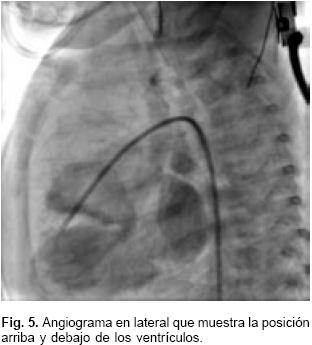

El estudio hemodinámico corroboró los diagnósticos y demostró que las presiones en ambos ventrículos, la arterial pulmonar y de la aorta eran las mismas; la presión sistólica sistémica fue de 50 mm Hg. Se evidenció una comunicación interventricular trabecular pequeña. El gradiente entre el arco aórtico y la aorta descendente fue de 17 mm Hg, con coartación aórtica yuxtaductal e hipoplasia importante del istmo aórtico y de la porción horizontal del arco; se confirmó la permeabilidad del conducto arterioso (Figs. 4, 5 y 6). La resonancia magnética nuclear hizo más relevantes las características anatómicas, para presentar el caso al Servicio de Cirugía (Fig 7).